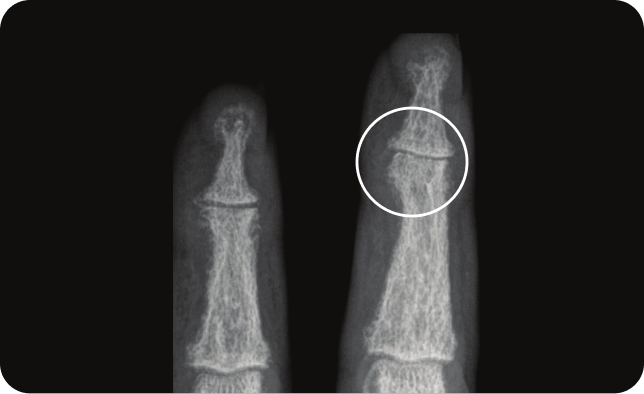

The TRANSFIGURE study was conducted to evaluate the efficacy and safety of Cosentyx in patients with moderate-to-severe nail psoriasis.

Randomization was managed via a central interactive randomization system and ensured that an equal number of patients were allocated to Cosentyx 300 mg, Cosentyx150 mg or placebo, stratified by body weight (< 90 kg or 90 kg). At week 16, all patients receiving placebo were rerandomized 1:1 to receive either 300 mg or 150 mg Cosentyx.

Patients received subcutaneous treatments of identical appearance once a week for 5 weeks (at baseline and weeks 1, 2, 3 and 4), followed by dosing every 4 weeks, starting at week 4.3

The Primary endpoint was to demonstrate the superiority of secukinumab over placebo, as assessed by the percentage change in total fingernail NAPSI score from baseline to week 16 =45.3, P<0.0001.3

*(HR 2.93, 95% CI 1.68 –5.12) than subjects without nail dystrophy.

†Mean baseline NAPSI score was 42.6.3

QW=every week; Q4W=every 4 weeks.